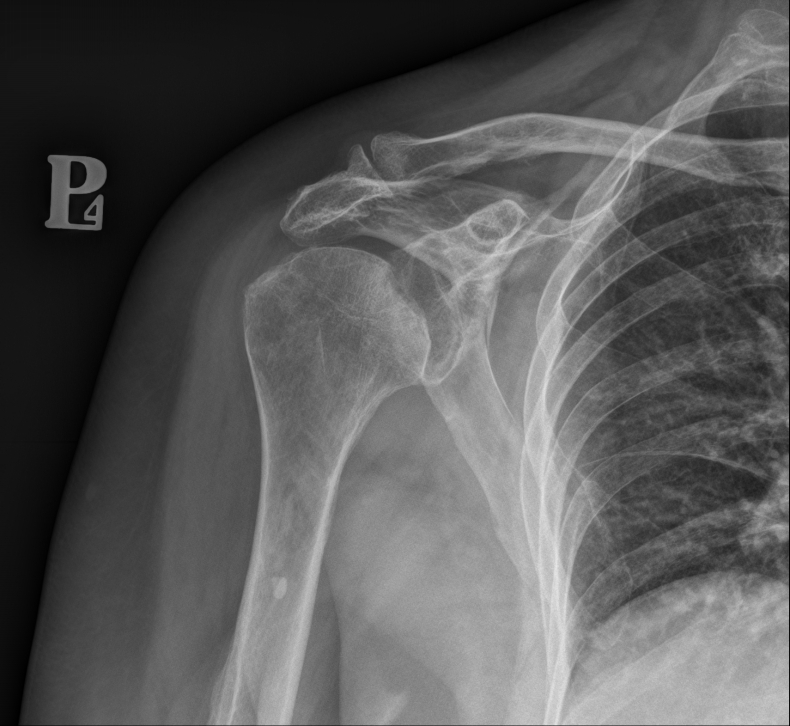

Konsultacja radiologiczna narządu ruchu to bezpośrednia rozmowa z radiologiem, która wykracza daleko poza standardowy opis badania. To spotkanie, podczas którego lekarz radiolog szczegółowo analizuje obrazy z badań diagnostycznych (rezonans, tomografia, RTG), wyjaśnia znaczenie widocznych zmian i odpowiada na pytania Pacjenta. W przeciwieństwie do tradycyjnej ścieżki, gdzie opis trafia bezpośrednio do lekarza prowadzącego, konsultacja daje Pacjentowi możliwość bezpośredniego kontaktu z osobą, która analizowała jego badanie. To usługa, która pomaga zrozumieć wyniki, rozwiać wątpliwości i uzyskać pełen obraz swojego stanu zdrowia.

Zrozumienie medycznego żargonu – opisy radiologiczne pełne są hermetycznej terminologii, która brzmi groźnie, nawet gdy nie musi być powodem do niepokoju. Radiolog pokazuje na konkretnych obrazach, gdzie znajdują się zmiany i co one rzeczywiście oznaczają.

Obiektywna ocena zmian – radiolog potrafi odróżnić zmiany istotne klinicznie od naturalnych procesów starzenia się organizmu, które nie wymagają leczenia. Wiele zmian widocznych w badaniach to po prostu skutki upływu czasu, niekoniecznie powodujące objawy.